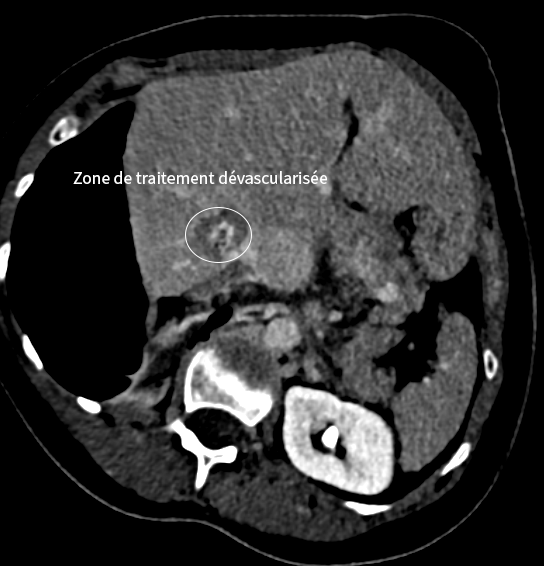

Traitement hépatique par micro-ondes

Dans un second temps, la métastase hépatique est traitée par thermoablation micro-ondes, avec protection des organes voisins grâce à une technique d’hydrodissection.

En images

Images du traitement des organes (poumon et foie) avant, pendant et après le traitement.